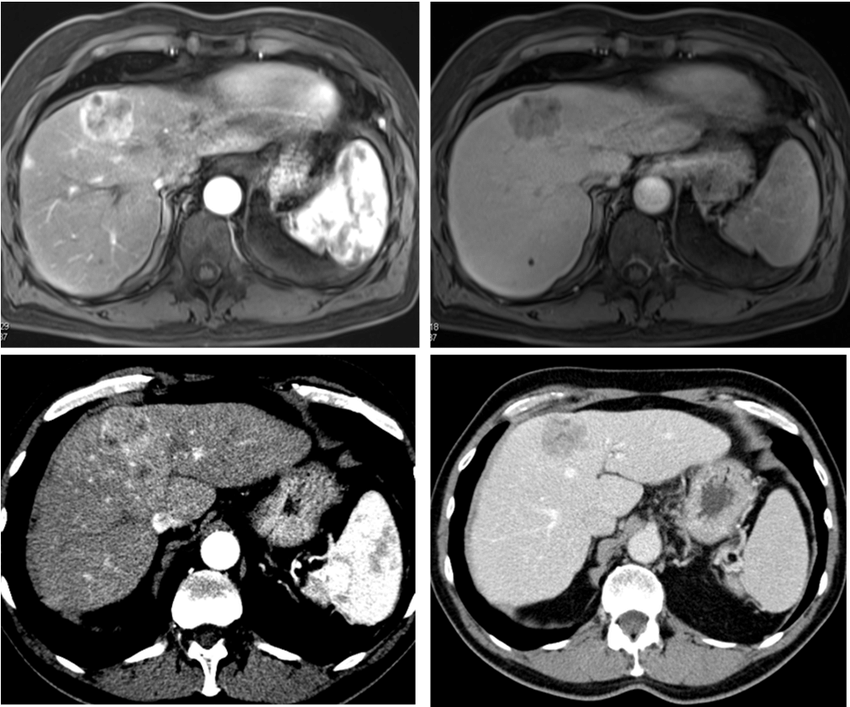

Nella Fase attiva dell'Endoderma si ha la crescita di tessuto supplementare al fine di assimilare tutto quello che si è mangiato per approfittare del momento di magra. In Fase di riparazione il tessuto in più viene smantellato con l'aiuto dei Batteri oppure viene incistato e calcificato. Va ricordato che se la lesione è una sola l'SBS è riferito ad altri. Se le lesioni sono multiple l'SBS è riferito a se' stessi.

Nella Fase attiva delle attivazioni ectodermiche c'è ulcerazione delle vie biliari per far passare più Bile che poi serve a marcare il Territorio in modo deciso. In questa fase fa male il Fegato, si possono avere delle coliche. Nella Fase di riparazione queste ulcerazioni vengono riparate con un po' di eccedenza di tessuto che potrebbe andare ad ostruire i vasi biliari e determinare l'Ittero.